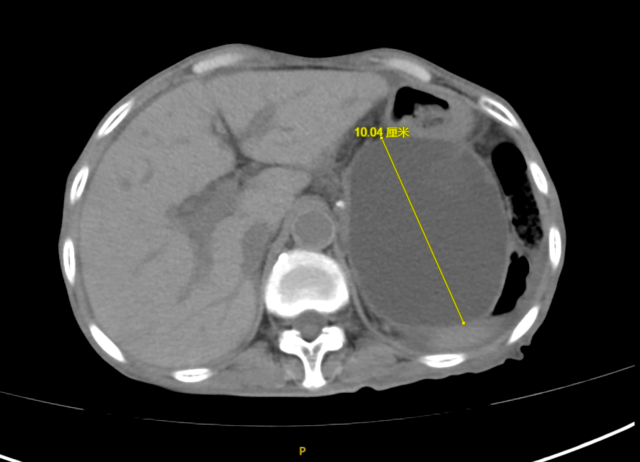

程女士,70岁,反复腹胀4天余,来到昆山市一医院消化内科就诊,通过问诊得知程女士去年7月因“急性腹痛发作”于外院确诊为急性重症胰腺炎,经治疗后,胰腺炎病情虽有好转,但不幸的是:程女士出现了胰腺炎治疗后的并发症——胰腺假性囊肿,门诊复查腹部CT提示胰尾部假性囊肿形成,大小约10*8.5cm,程女士此次腹胀、恶心呕吐考虑是由于巨大囊肿压迫所致。程女士此前已辗转于昆山及周边多家医院就诊,由于程女士年龄大,病情重,大量腹水(超声腹水深度为12cm),营养差,白蛋白16.3g/L(正常值:35-50g/L),行进一步手术治疗风险极大,程女士和家属焦急万分。

手术后

术后程女士腹痛、腹胀症状迅速得到了缓解,复查CT示囊肿较前显著缩小,目前已康复出院。